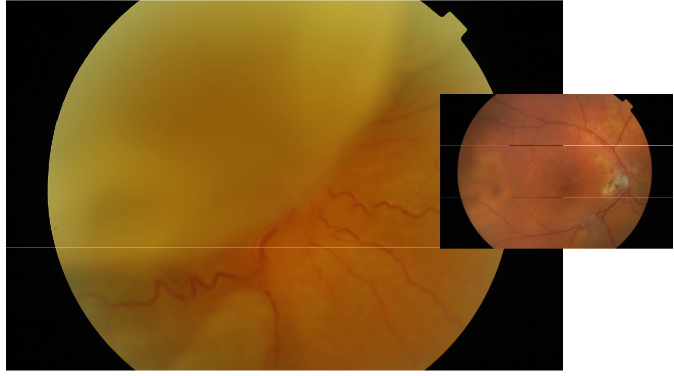

What is this condition

All RD

2nd pic=Tractional

3rd pic=Exudative-pockets where the retina has come off, fluid under retina in the subretinal space

What are the types and causes of retinal detachment?

Rhegmatogenous Retinal Detachment (RRD)

Cause: retinal break

Tractional (TRD, retina pulled away by contracting vitreoretinal membranes eg ERM)

Causes: proliferative DR, retinopathy of prematurity, toxocariasis, trauma, previous giant retinal tear

Exudative (fluid derived from the choriocapillaries gains access to subretinal space)

Causes: neoplastic choroidal lesions, inflammatory disease, optic pit, choroidal coloboma, vascular disorders, nanophthalmos